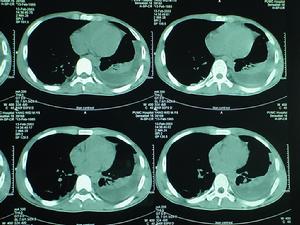

x線胸片檢查

煤塵肺X光片煤工塵肺中不論是煤矽肺還是煤肺,x線胸片上主要表現是類圓形小陰影、不規則形小陰影和大陰影。除此,還可見到肺紋理、肺門陰影的異常變化,但多缺乏特異性,也只能作為判斷塵肺的類型參考之用,不能視為依據。

(3)大陰影:煤塵肺患者胸片上常能見到大陰影。在系列胸片上可看到,煤矽肺患者大陰影形成多是小陰影的增大、密集、融合或由“斑、片、條”或“發白區”最後成為緻密的團塊狀陰影,邊界清晰,呈橢圓形、長條形或圓形,並在其周邊部看到有氣腫帶,多在兩肺上中區,左右對稱。煤肺晚期則罕見大陰影。此外,煤工塵肺多為瀰漫性、局限性或泡性的肺氣腫,表現為成堆小泡狀明影,直徑多為l-5MM,即所謂“白圈黑點”。煤肺、煤矽肺多見泡性肺氣腫。肺門陰影增大,密度增高,有時還可見淋巴結蛋殼樣鈣化或桑椹樣鈣化陰影。胸膜增厚、鈣化改變者雖不多見,但常可見到肋隔角閉鎖和粘連。煤工塵肺按《塵肺X線診斷標準》進行診斷和分期。